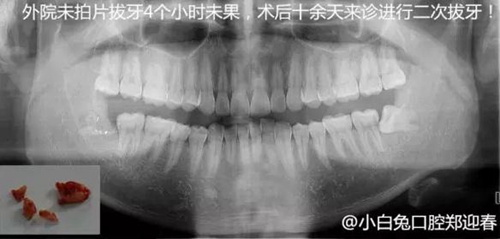

下面看一個病例,患者,女,30歲,因左下頜智齒嵌塞食物后疼痛,至當(dāng)?shù)匮揽平o予拔除,但術(shù)后1個半月,患者自覺拔牙區(qū)一直隱隱疼痛,時輕時重,遂來診。檢查發(fā)現(xiàn),拔牙創(chuàng)口一直未愈合,未見明顯腫脹,拍片發(fā)現(xiàn),拔牙窩內(nèi)顯示高密度斷根影

像,該斷根臨近下頜神經(jīng)管,同時發(fā)現(xiàn)第二磨牙遠中有兩塊高密度影像,疑似殘留骨片或牙片,應(yīng)該是引起疼痛的原因,經(jīng)與患者溝通,采納建議,進行二次拔牙。